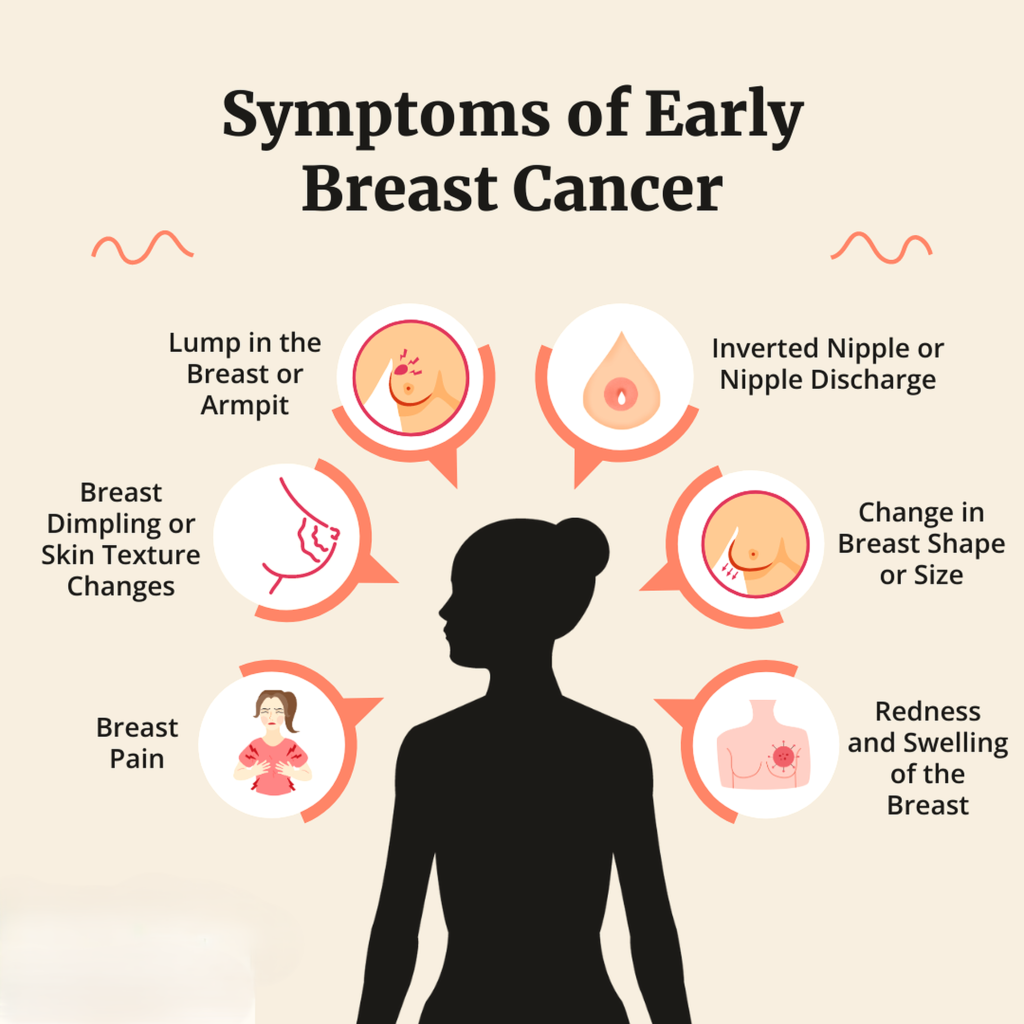

- Lump that does not go away

- Rapidly growing lump

- Lump associated with pain, skin changes, or discharge